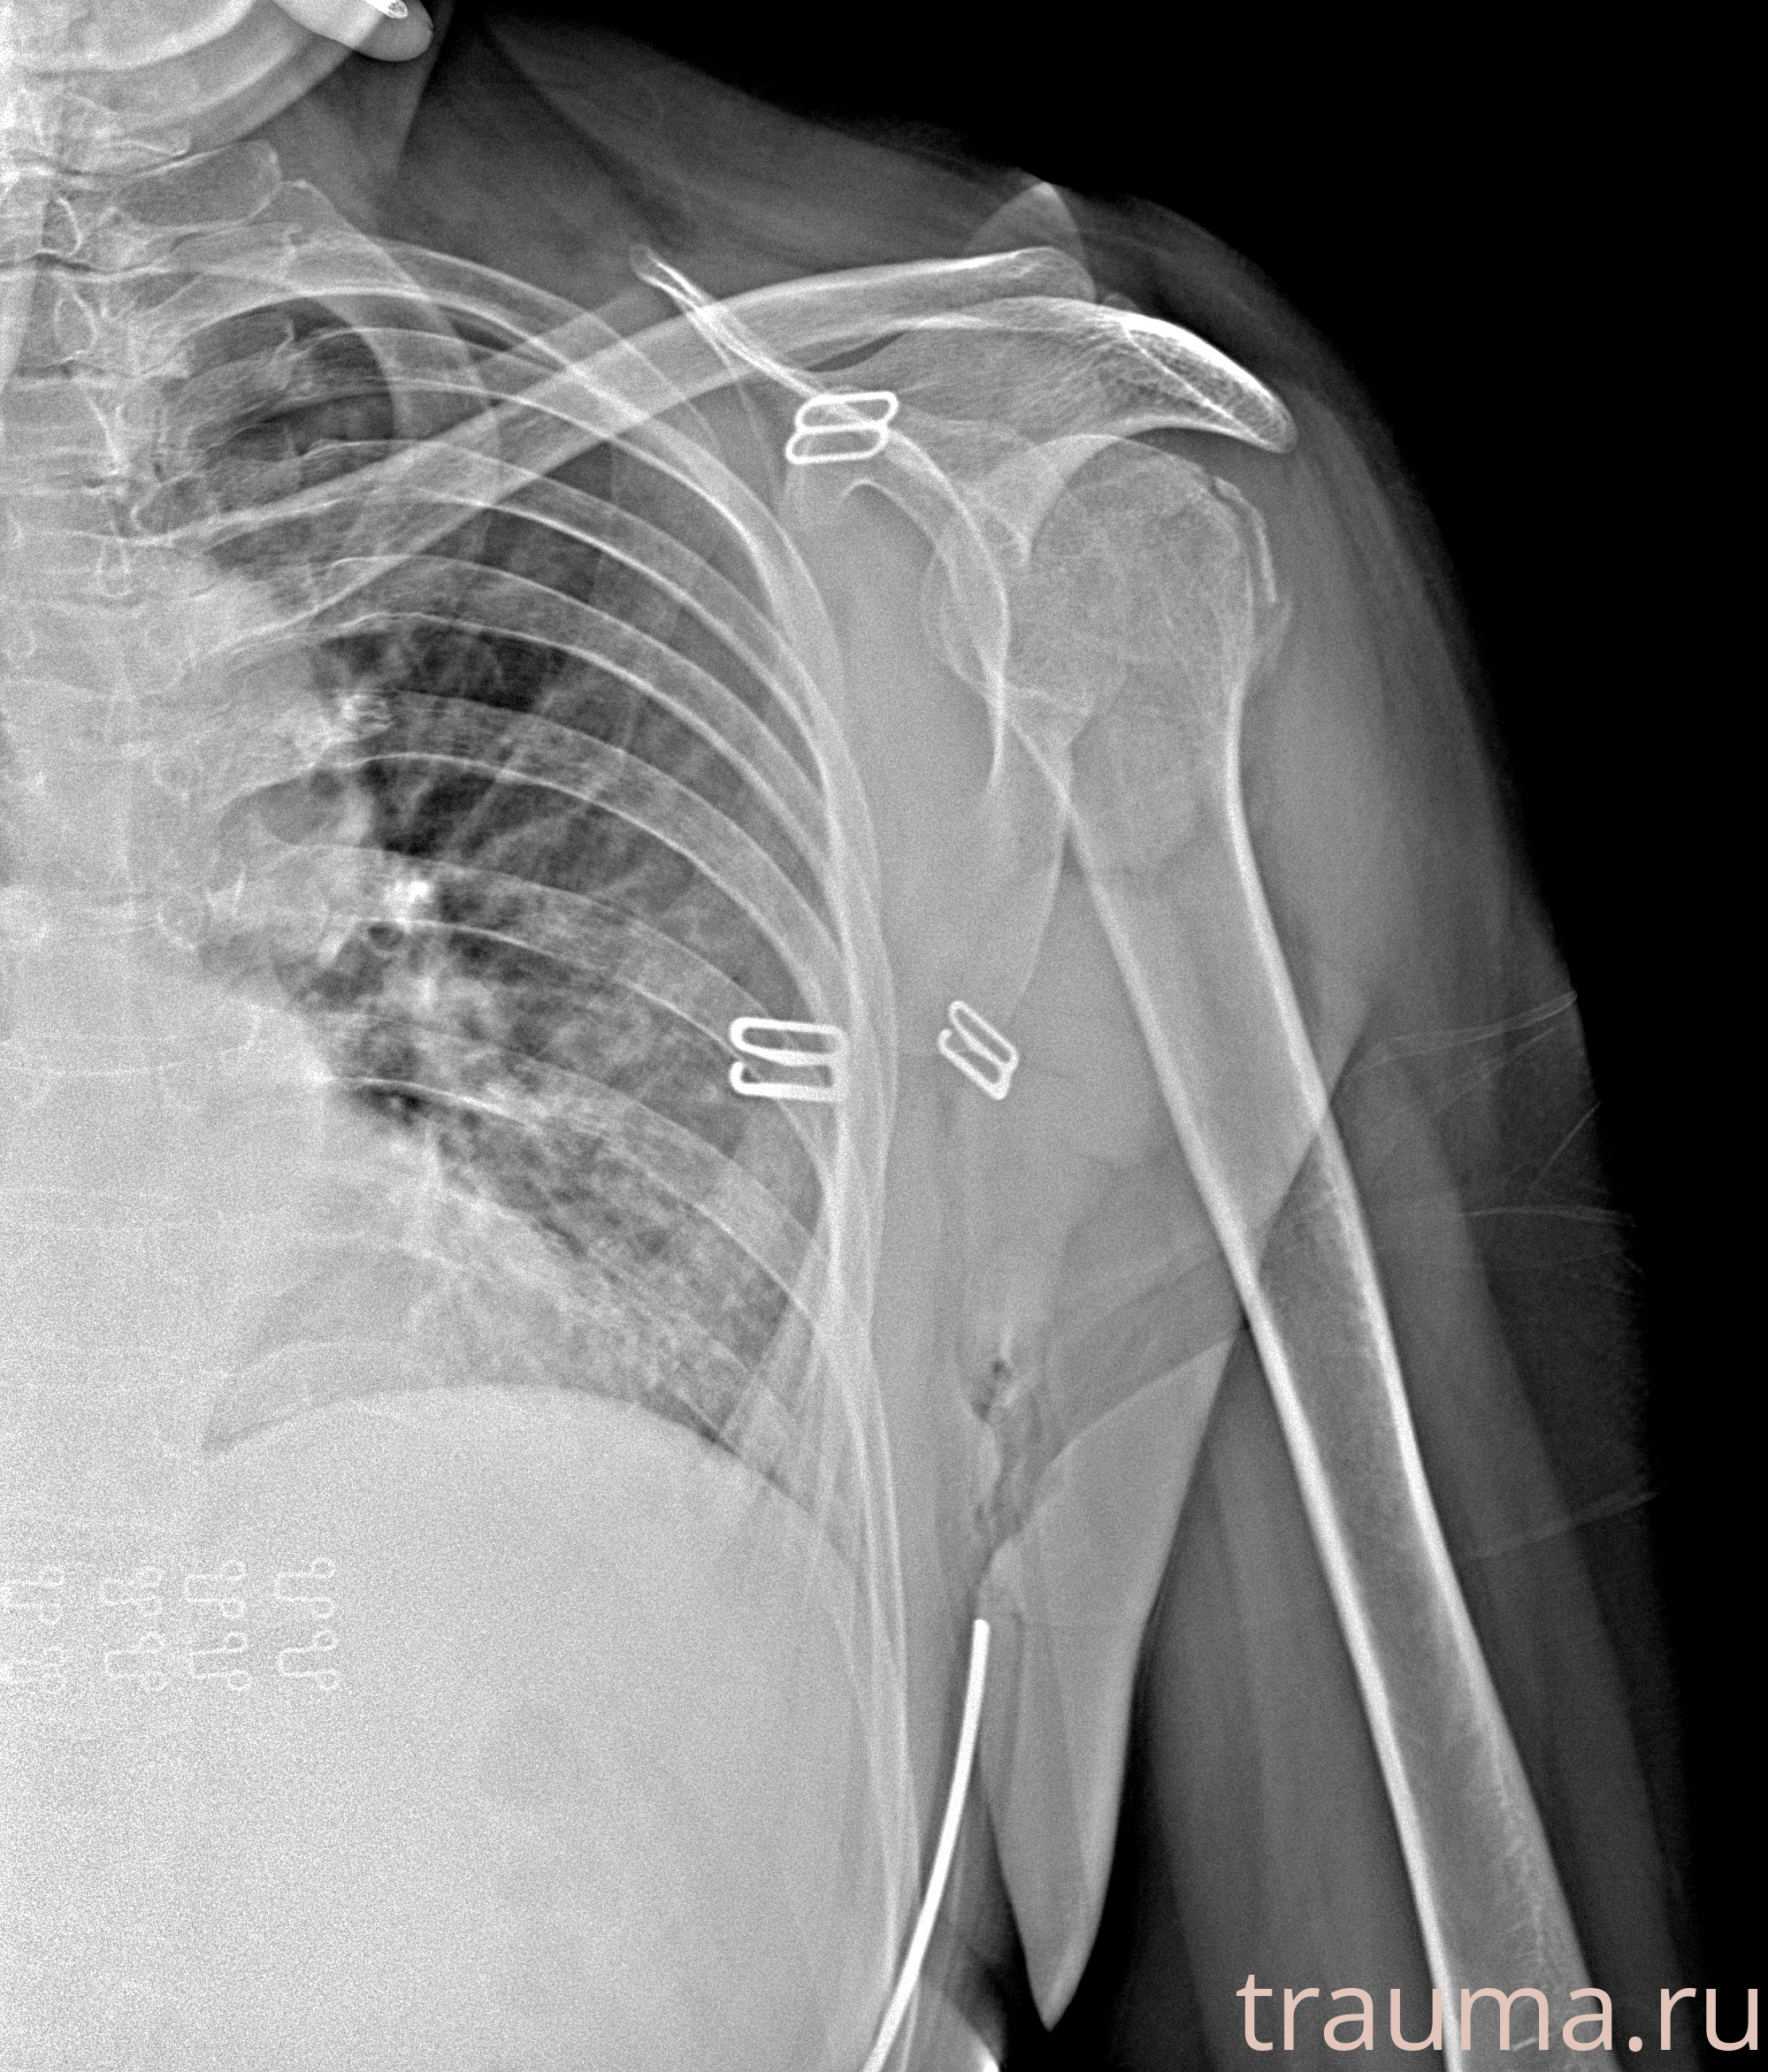

Рентгенограммы

Рентген на дому: по вашему адресу приезжает врач-рентгенолог, травматолог-ортопед с мобильным рентгеновским аппаратом, проводит диагностику травмы или заболевания, делает необходимые рентгенограммы, дает рекомендации по дальнейшему лечению. Получить качественные снимки в домашних условиях возможно благодаря уникальной методике, разработанной МосРентген Центром для института  Склифосовского